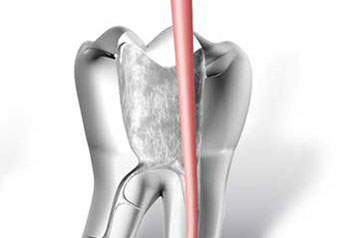

• asportazione della polpa e sagomatura dello spazio endodontico con strumenti meccanici (in nichel-titanio), con l'ausilio della detersione del canale radicolare (acqua ossigenata, ipoclorito di Sodio, calcio-chelanti)

• otturazione di tutto l'endodonto mediante materiali termoplastici (guttaperca) e cementi biocompatibili